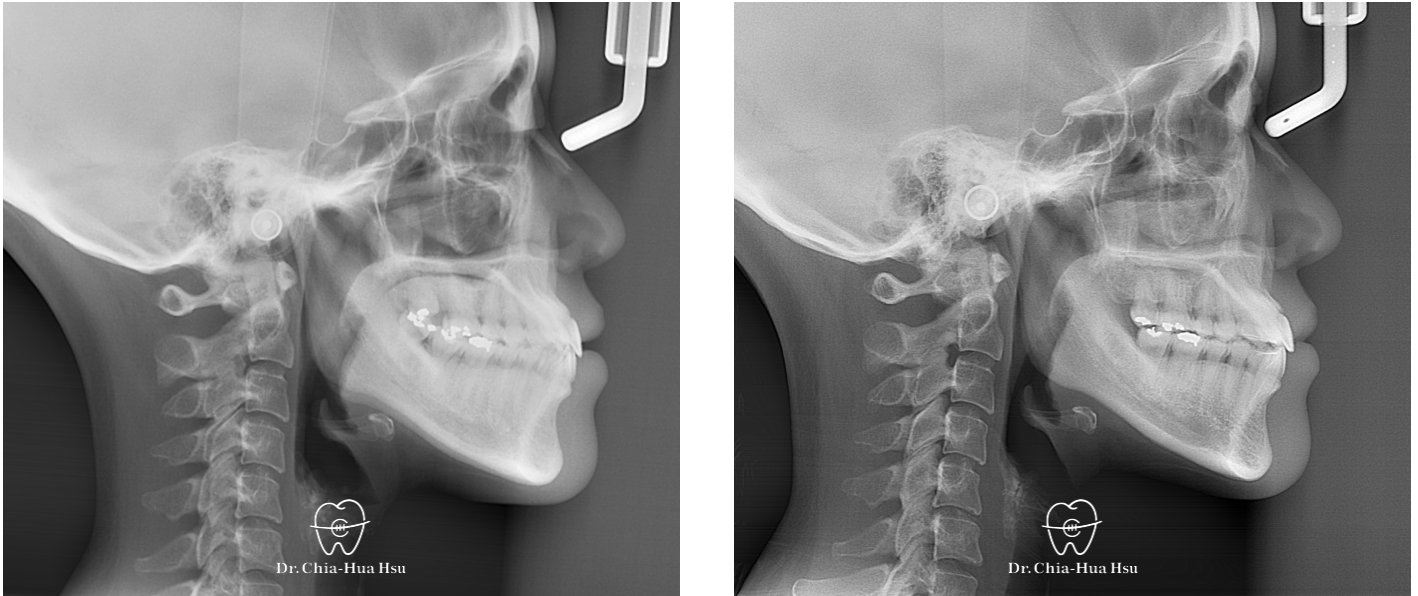

錯咬、齒列擁擠

成人矯正 | ⾦屬矯正 | 非拔牙治療 | 骨釘

治療前

治療後